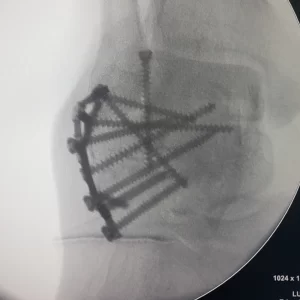

Placa INNOBLOX

Sistema 3.5

Para Calcáneo

Fractura desplazada del cuerpo del calcáneo, Simples

articulares e intraarticulares.